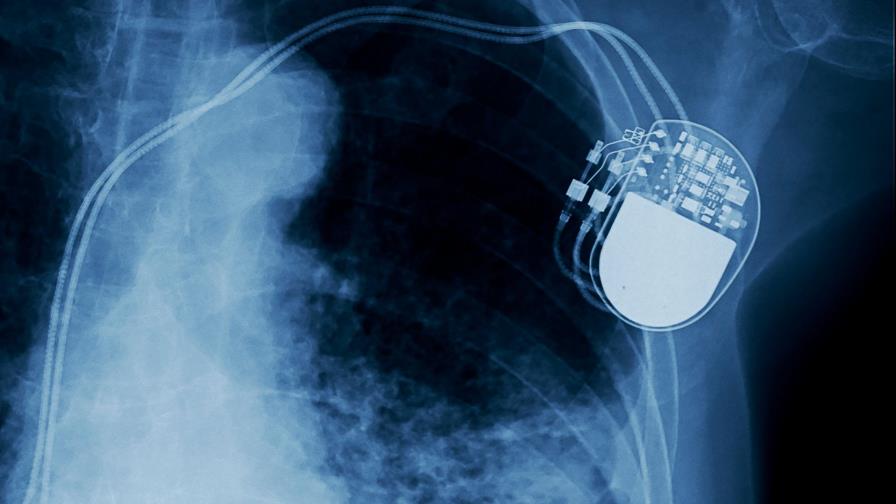

Expertos prueban en cerdos adultos un marcapasos sin pilas

Un equipo de expertos ha implantado en cerdos adultos un marcapasos que funciona sin pilas y que extrae la energía de la moción cardíaca, según un estudio divulgado en el último número de la revista Nature publicado este martes.

Los marcapasos actuales y otros dispositivos médicos semejantes funcionan con pilas que abultan, son rígidas y tienen una corta duración.